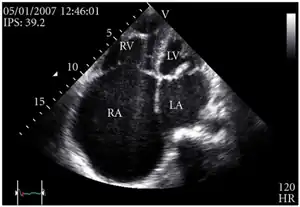

Transthoracic echo: enlargement of the right atrium in TR and mitral valve disease